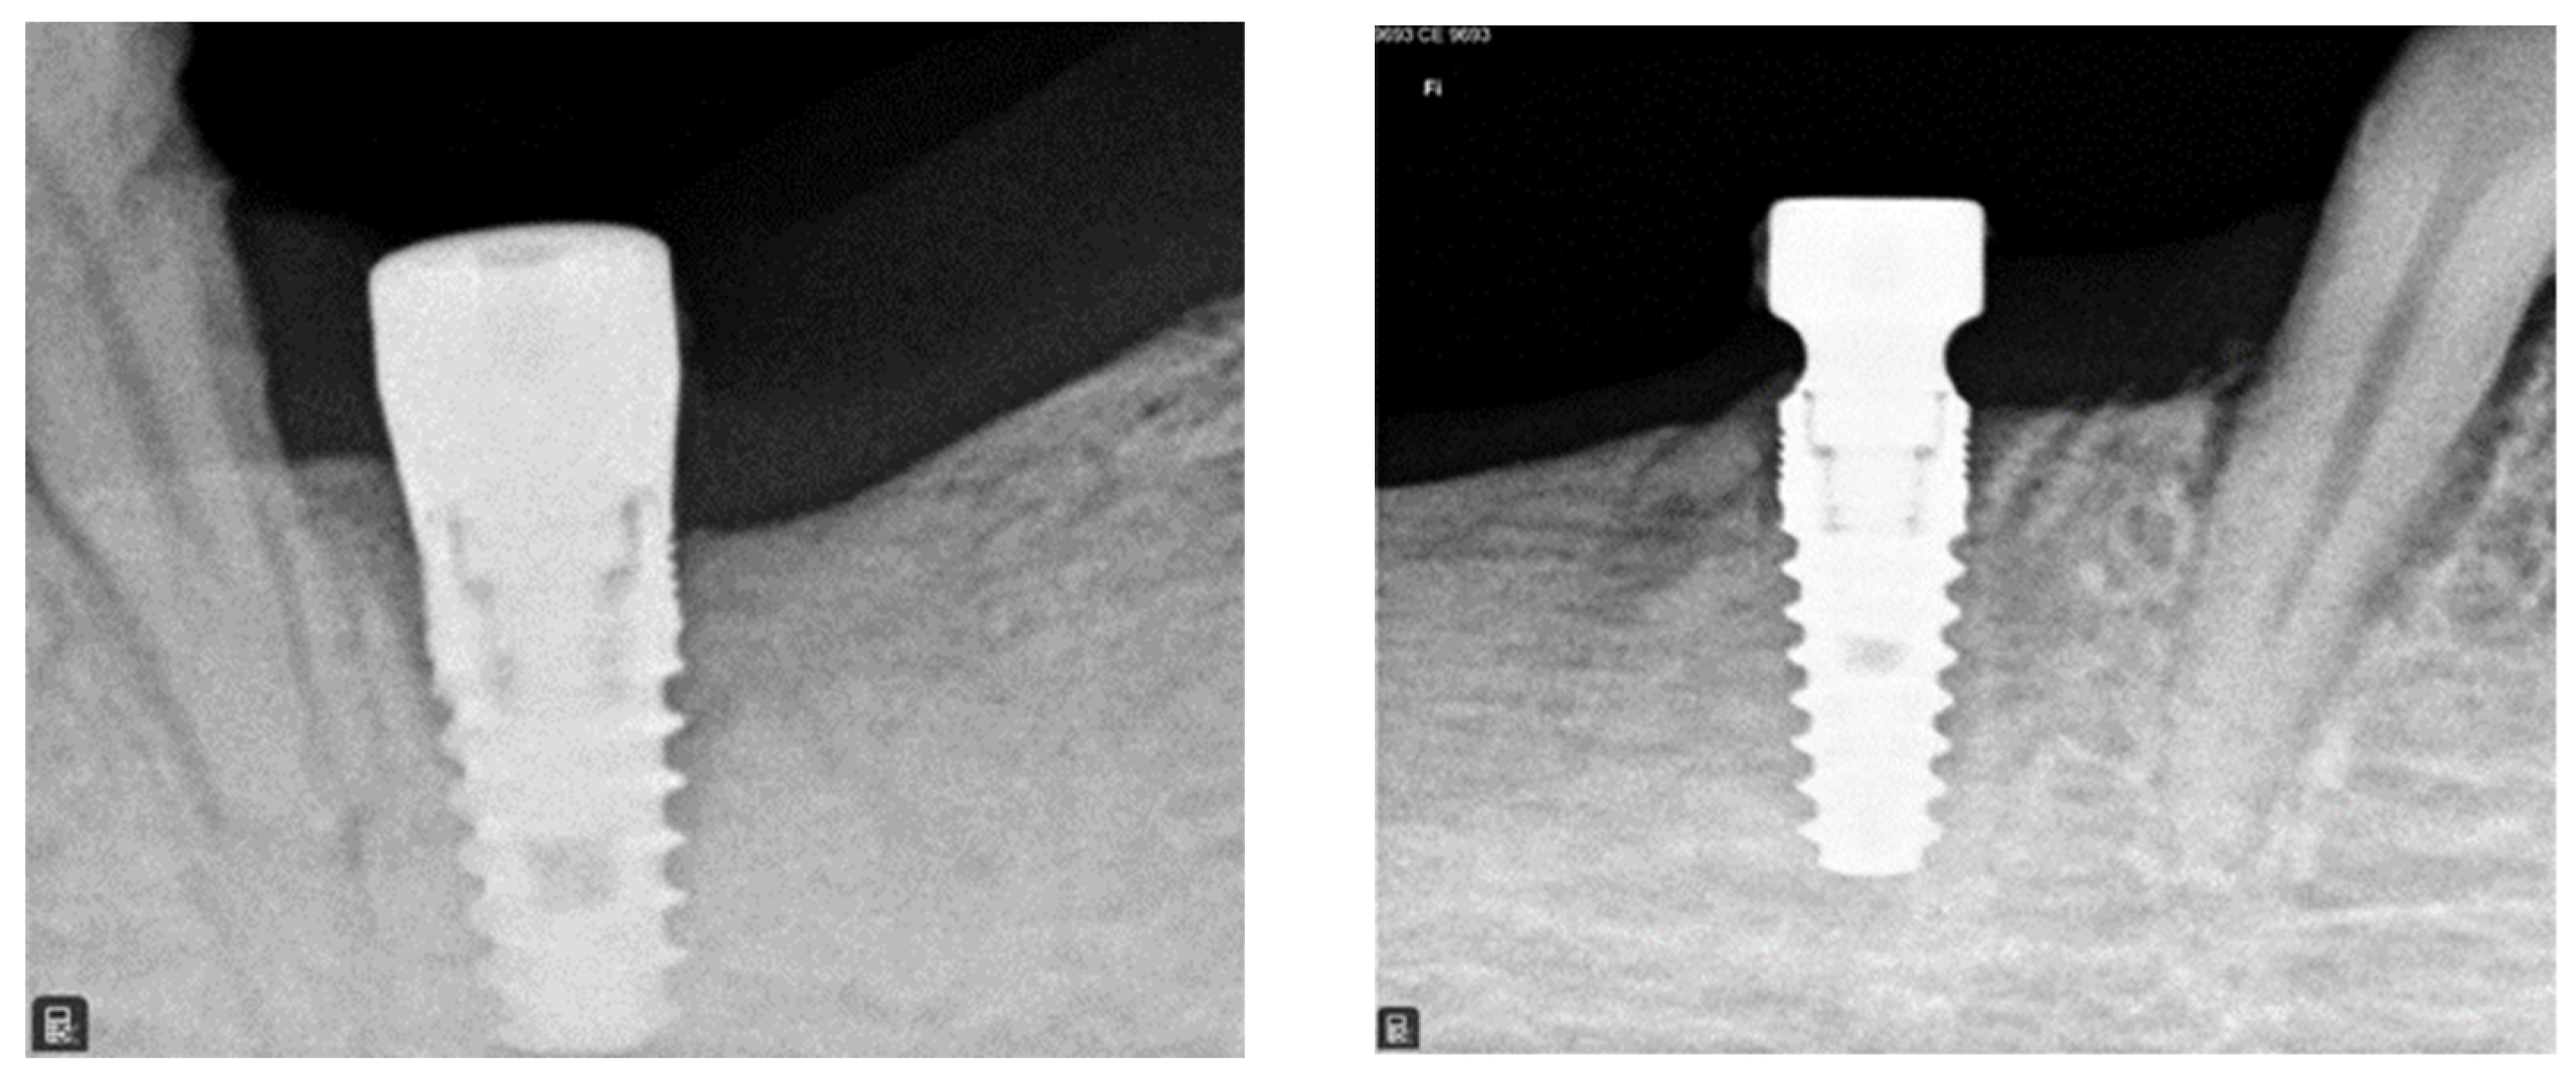

3.1. Radiographic Analysis

3.2. Histological Analysis